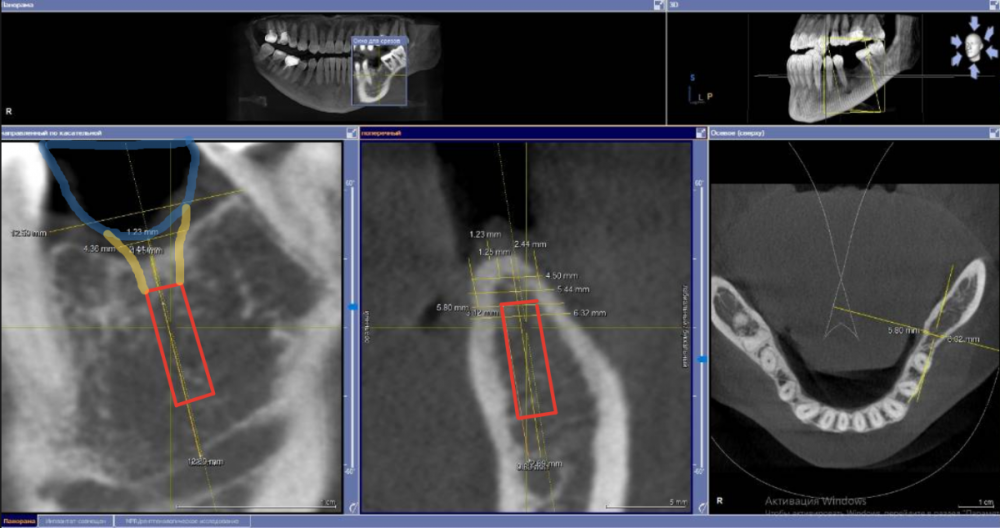

Fin Опубликовано 28 июня, 2021 Поделиться Опубликовано 28 июня, 2021 (изменено) Коллеги как бы Вы решили данную ситуацию? Давно хочу начать ставить поставить анкилос. Кто ставит как Вам клин ситуация для 3.5Х8 с заглублением в 3 мм? Пока склоняюсь к импланту диаметорм 4,5 заглубление (2 мм) и небольшой НКР спейсер+титановая сетка) потом работа с десной. Или все же поставить 4 на 8,5 +ССТ с заглублением 2,5 мм без НКР. Навигац шаблон во всех вариантах. Изменено 28 июня, 2021 пользователем Fin Ссылка на комментарий

Fin Опубликовано 28 июля, 2021 Автор Поделиться Опубликовано 28 июля, 2021 Подниму тему, немного пропал. Был в отпуске без интернета, а потом отходил от отпуска пару недель. 07.07.2021 в 23:53, АнтонТЛТ сказал: Я сотни 4.0 в моляры ставил и всё было хорошо, 3.5 тоже приходилось. Пока без проблем было. На оригинальной протетике переломов винта и имплантата у меня не встречалось. Что использовалось в данном случае, лучше спросить у Олега. В его клинике делалась работа в 16 году. Вы бы поставили 4ку в данном случае? 08.07.2021 в 21:26, Bier сказал: Сюда легко и 4.0 и 4.5 войдет. Надо выяснять. Но тут недозаглублен имплантат. ? Что делать, раньше так ставили. Я думаю, что в этом проблема. Лизис кости и затем перелом. В ширину 5.8 имплант 4.5. Вы имеете ввиду частично оголить вестибулярную часть импланта и поработать с десной? Ссылка на комментарий

Bier Опубликовано 30 июля, 2021 Поделиться Опубликовано 30 июля, 2021 28.07.2021 в 22:33, Fin сказал: В ширину 5.8 имплант 4.5. Вы имеете ввиду частично оголить вестибулярную часть импланта и поработать с десной? ну если ширина гребня 5.8 а диаметр препаровки ложа примерно 4.1-4.2 с чего вы взяли, что вестибулярная часть имплантата обнажится? Ссылка на комментарий

Fin Опубликовано 2 августа, 2021 Автор Поделиться Опубликовано 2 августа, 2021 (изменено) 30.07.2021 в 22:17, Bier сказал: ну если ширина гребня 5.8 а диаметр препаровки ложа примерно 4.1-4.2 с чего вы взяли, что вестибулярная часть имплантата обнажится? Благодарю за ответ. Все верно. Но если брать информацию того же Томаса Линчкевикуса он советует что бы минимум был 1 мм кости вокруг. Следовательно делаем 1 мм с язычной поверхности то с щечной поверхности будет около 0,3(грубо говоря нет). Изменено 2 августа, 2021 пользователем Fin Ссылка на комментарий